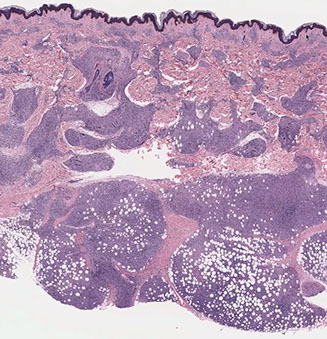

Hailey-Hailey disease

Micro: "dilapidated brick wall" appearance of acantholysis

- also see acanthosis

AD inherited dz (ATP2C1 gene [for a Ca2+ pump]) c poor cellular adhesion; a genodermatosis (??)

- "wet tissue paper" look of affected skin in neck and intertriginous areas; not as diffuse as Hailey-variant of Grover's disease

- acantholysis should NOT involve the hair follicle (if it does, then the dx is probably pemphigus vulgaris)